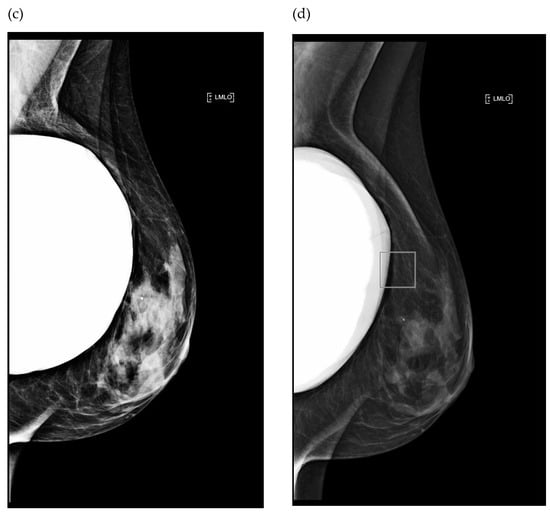

3.1.1. Impact of Breast Implant Radiopacity According to Acquisition Technique Based on the Recommended Settings Compared to the Reference Settings

3.1.2. Impact of Breast Implant Radiopacity According to Acquisition Technique Based on the Recommended Settings Compared to the Misused Settings